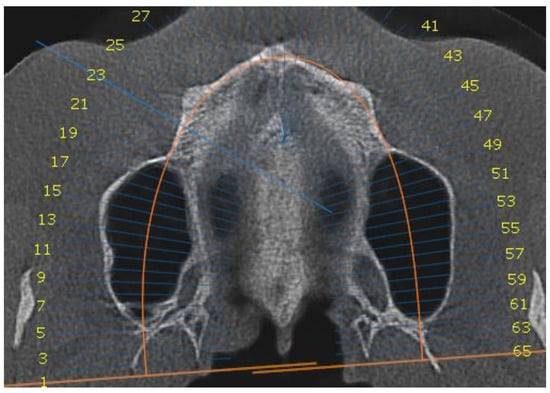

2. Material and Method

2.1. Outcome Measures

2.2. Clinical Outcomes